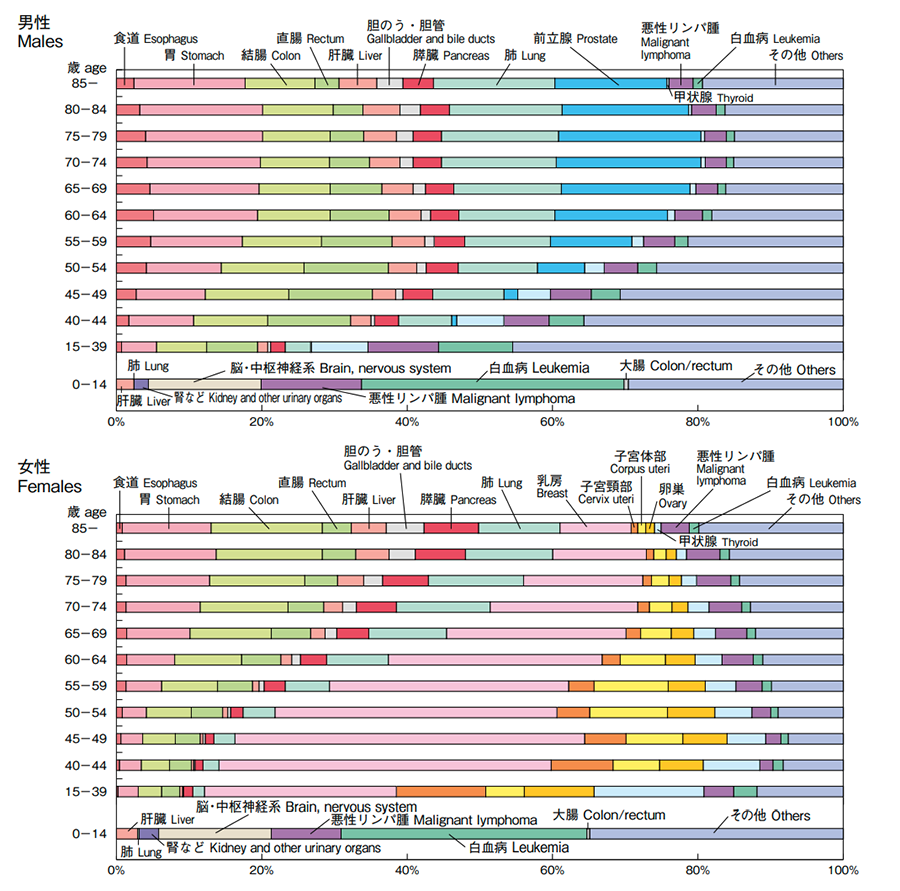

がんにかかっている人(罹患者)全体と比較すると、肺がんは、男性、女性ともに、高齢になるほどその割合が大きくなることがわかっています。

下表は、2018年度に新たにがんと診断された患者さんのがん種を年齢層別に見たものです。男性では、40歳以上で消化器系(胃、大腸、肝臓など)のがんが5〜6割を占めますが、70歳以上では肺がんと前立腺がんの割合が大きくなっていることがわかります。女性では、40歳代で乳がんが約5割、子宮がんと卵巣がんが合わせて約2割を占めますが、年齢層が上がるほどそれらの割合は小さくなり、肺がんと消化器系のがんの割合が大きくなっています。

年齢階級別 がん罹患部位内訳 (2018年)